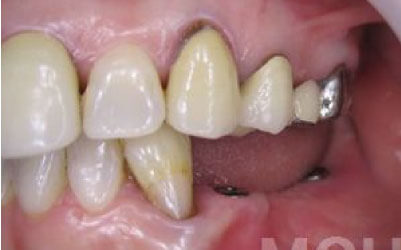

歯が抜けた後の治療について、多くの方が悩まれています。

特に、抜けたのが前歯ですとなおさら気になりますよね。 今回のご質問ですが、抜けた部分の骨が薄いなどの理由で「インプラントはできない」と言われた可能性があります。

前歯はもともと骨が薄く、歯が抜けると時間の経過とともにさらに骨が痩せてきてしまうので、インプラント治療の難易度が高い場所です。 ただ結論からお話すると、インプラント治療は可能です。

なぜなら、もし仮に骨が薄くても、骨の治療によって厚みが増せば、安全にインプラント治療が行えるからです。

なお、前歯のインプラント治療をご希望の方には、注意していただきたい点が4つほどあります。 1)インプラント治療を行う前に、骨の治療が必要かもしれません。

2)骨の治療から始めると、その分、治療期間が長くなります。

3)骨の治療は、通常のインプラント治療よりも難易度が高いため、経験の豊富な先生やインプラント認定医のいる歯科医院で治療を受けることをお勧めします。

4)骨の状況をしっかり把握するためにも、CT撮影が必須となります。 また、インプラント治療においては、周囲の歯の状況や咬み合わせの問題などもしっかりと考えて治療するのがとても大切です。

そのため、残っている歯についてもきちんと診査してくれるクリニックが良いでしょう。 インプラント治療には、「インプラントを入れたら終了」というイメージがありますが、治療後、どれだけ長くインプラントがもつのかが最も大切なことなので、しっかりとメンテナンスしてもらえる歯科医院を選んでください。 まずは、いくつかの歯科医院でインプラントの相談をして比較検討し、ご自身が良いと感じた先生のところで治療を受けることをお勧めいたします。